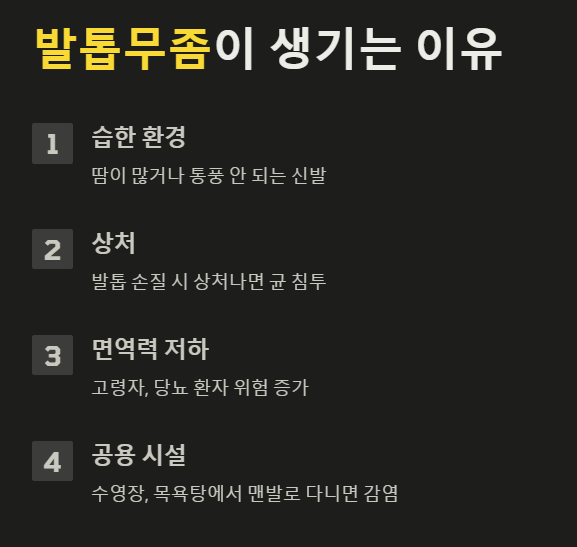

① 발에 땀이 많거나 습한 환경 유지

✔ 여름철, 땀이 많거나 통풍이 잘 안 되는 신발을 오래 신으면 곰팡이균이 번식하기 좋아요.

✔ 운동화, 군화, 구두처럼 밀폐된 신발을 오래 신는 경우 더 쉽게 생겨요.

② 손발톱을 다치거나 손질할 때 상처가 난 경우

✔ 발톱을 너무 짧게 깎거나, 무리하게 큐티클을 제거하면 균이 침투할 틈이 생겨요.

✔ 특히 발톱이 부러지거나 금이 간 경우 무좀균이 쉽게 들어갈 수 있어요.

③ 면역력이 약해진 경우

✔ 고령자, 당뇨 환자, 면역력이 떨어진 사람은 발톱무좀이 생길 위험이 더 커요.

✔ 손발톱으로 가는 혈액순환이 원활하지 않으면 균이 더 쉽게 번식할 수 있어요.

④ 공용 시설(수영장, 목욕탕, 사우나) 이용

✔ 발톱무좀은 전염성이 강한 질환이라, 감염자가 맨발로 다닌 곳에서는 균이 쉽게 퍼질 수 있어요.

✔ 특히 수영장, 목욕탕, 헬스장 샤워실 같은 곳에서 맨발로 다니면 감염될 가능성이 커요.